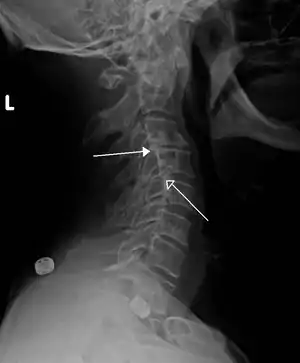

![]() | |

| Grade 1 retrolistheses of C3 on C4 and C4 on C5 | |